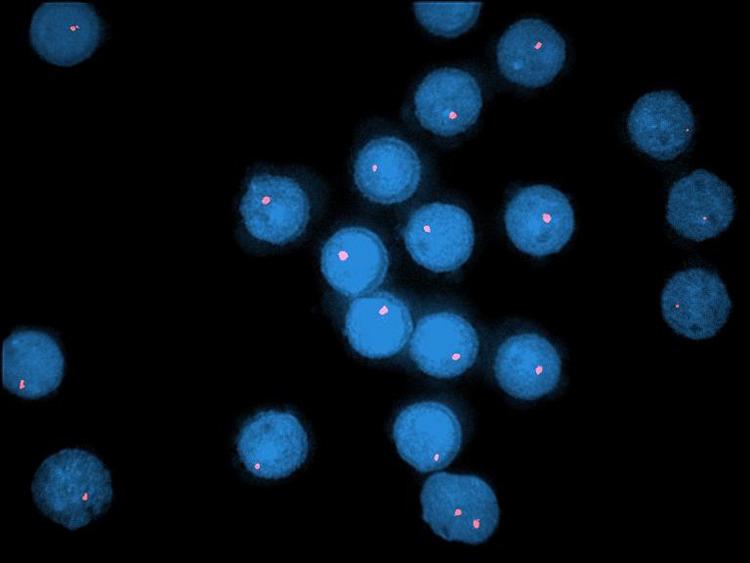

Chronic lymphocytic leukemia (CLL), with an incidence rate between 4 and 6 cases per 100,000 persons per year, is considered the most prevalent leukemia in the western world. Chemoimmunotherapy (such as fludarabine, cyclophosphamide, and rituximab), bendamustine plus rituximab, and, more recently, novel agents such as ibrutinib (Bruton tyrosine kinase inhibitor), idelalisib (phosphatidylinositol-3-kinase δ inhibitor), and venetoclax (BCL-2 inhibitor) have changed the management of CLL. Shanafelt and colleagues compared the efficacy of ibrutinib-rituximab with that of standard chemoimmunotherapy in patients with treatment-naïve CLL. They did not, however, mention that the therapy varies on the basis of where patients live and, given that local guidelines not immediately reflect US Food and Drug Administration (FDA) updates, discrepancies in treatment occur. Important CLL goals are the availability of rapidly reproducible tests, standardization of national and international guidelines, and FDA approval-based treatment reimbursement.